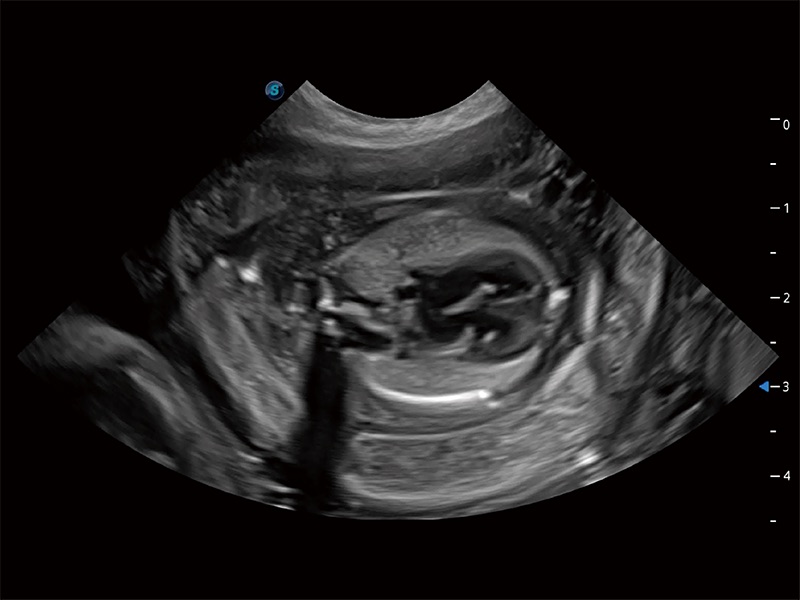

动物是人类最亲密的朋友和最值得信赖的伙伴。玖鼎集团也一直致力于探索动物专用的超声影像解决方案。全新推出的ProPet系列,是玖鼎集团在动物超声影像智能化、专业化、精准化的一次跨越式革新。动物不能用言语来表述自己的不适,通过超声影像,ProPet系列搭建了动物医生与不同物种沟通的“桥梁”,为动物医生注入了“治愈之力”。 ProPet 80 是玖鼎集团匠心打造的一款高端动物专用彩超,采用性能卓越的全新硬件架构,极大提升超声系统的运行效率和数据处理能力,帮助动物医生从容应对日益增多的挑战性病例和日益多样化的临床需求。

高性能和先进的临床应用工具可以为动物医生提供临床信心。ProPet 80 搭载了先进的腹部和浅表应用工具,帮助医生在日常临床实践中发挥前所未有的作用。

ProPet 80 全新的动物超声智能软件和丰富的探头群,为动物医生提供了高清晰度和精细分辨率的图像,无论在宠物、马科、畜牧还是实验室动物等应用中都可以轻松应对,为您的日常工作带来满意的体验。